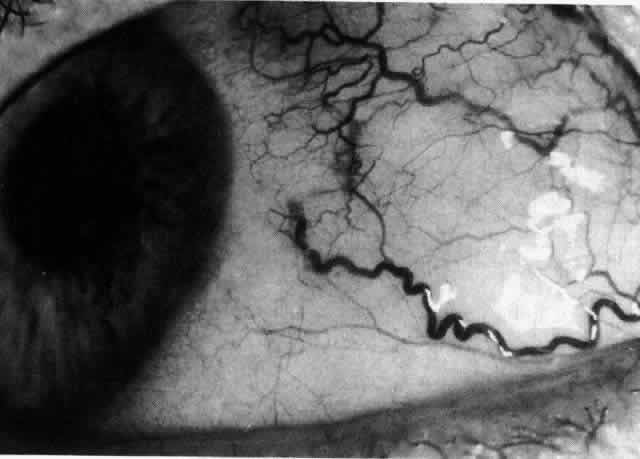

The sclera that is edematous is pushed forward, and the deep episcleral network is more congested than the superficial networks (Figs. 27 and 28). It is usually easy to ascertain by simple observation that the patient has scleritis and not episcleritis. However, it is not as easy to ascertain whether the patient has early necrotizing scleritis. It is in these patients that fluorescein angiography has considerable value, because the first changes are detectable in the ocular vasculature. Prompt and adequate treatment can prevent these changes from becoming irreversible.

Fig. 27. In scleritis, maximum congestion occurs in deep episcleral plexus, which is bowed forward by underlying scleral edema. Episcleral tissue is slightly infiltrated and superficial plexus is slightly congested (see Fig. 14). (Watson PG, Hayreh S, Awdry P: Episcleritis and scleritis. Br J Ophthalmol 52:278–279, 1968)

Fig. 28. Nodular scleritis. Both the anterior conjunctival slit and the deep scleral slit are displaced forward by the scleral edema. There is little separation between these two beams, indicating that all the edema is in the sclera and not in the overlying episclera. (Watson PG, Hayreh S, Awdry P: Episcleritis and scleritis. Br J Ophthalmol 52:278–279, 1968)

Diffuse Anterior Scleritis

Diffuse anterior scleritis is the most common and least severe type of scleritis. The inflammation is widespread, and it may involve either a small segment or the whole of the anterior segment, sometimes with such severe overlying inflammation as to justify the name “brawny” scleritis (Fig. 29). On slit lamp examination, the vascular pattern of both deep and superficial layers may be distorted, so that the normal radial pattern of the vessels is lost; large anastomotic channels develop, leading to beading and tortuosity of the remaining vessels (Figs. 30 and 31; Color Plate 1C).

Fig. 30. Diffuse anterior scleritis. During the acute attack, the vessels are dilated and distorted. New vessels or large vessels not normally seen have appeared adjacent to the limbus.

Fig. 31. Diffuse anterior scleritis after treatment. The dilated abnormal blood vessels remain even though no inflammation remains.

In this relatively benign form of scleral inflammation, the fluorescein angiogram reveals a rapid flow pattern in which the transit time of the dye is very rapid (as in episcleritis) (Figs. 32 and 33). Subtle changes occur in the capillary network, and abnormal leaking vessels appear after prolonged inflammation. These changes do not disappear after the inflammation subsides or is treated (see Fig. 31).